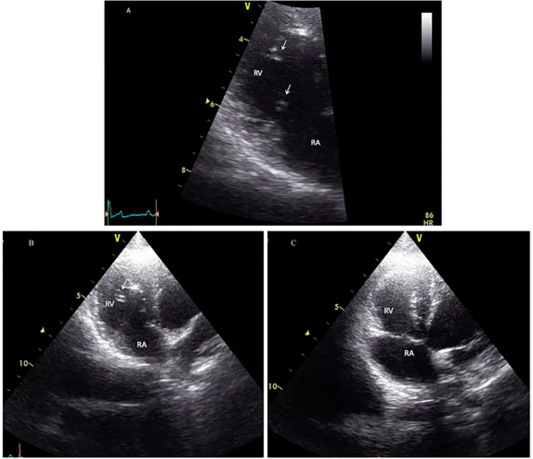

Echocardiographic image showing heartworms (white arrow) in the right ventricle of the infected cat (A and B) and after adult heartworm removal in C. Before the surgical intervention (A and B), heartworms (white arrow) are visible in the right ventricle (RV), no heartworm is visible after the procedure (C).